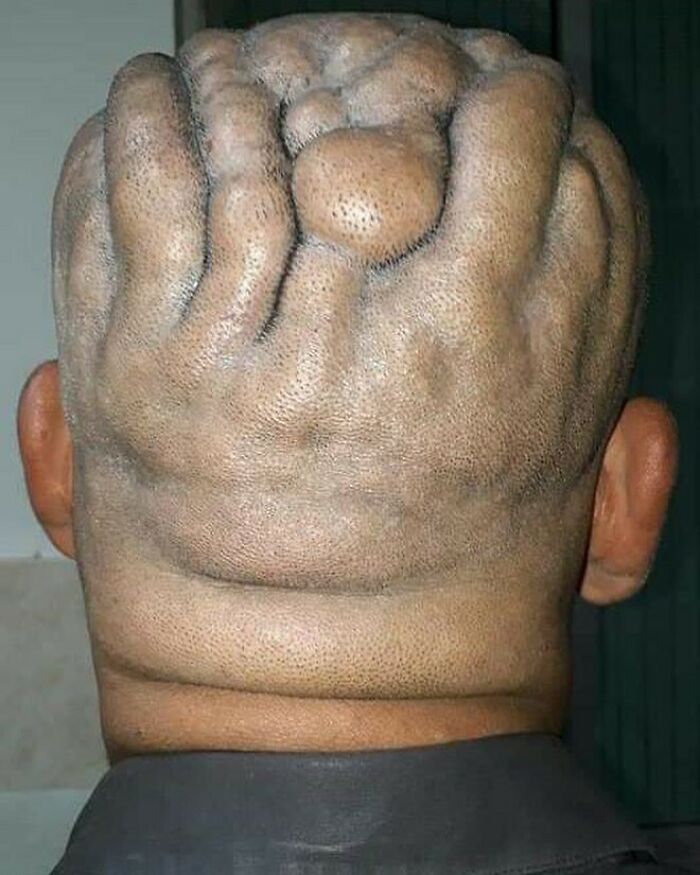

A 12-year-old immigrant female was admitted in the dermatology department with multiple brown lesions on the trunk and face and a large cerebriform plaque on the right side of her scalp.

She was born with multiple brown papules and nodules on the trunk and face and a brown patch on the right side of her scalp. She reported an increase in the size of the lesions on her body and face over time and there was no associated pain or itching. According to history given by her parents, the lesion on the scalp was a small brown flat patch at birth and had increased in size and thickness over the last 8 years and in the past 5 years it had become nodular and cerebriform. The patient complained of intense itching and discharge which had recently become malodorous.

Her birth and developmental history were normal.

In physical examination, her developmental and nutritional status was normal. The head circumference was in normal range and her neurologic, cardiovascular, musculoskeletal, and ophthalmic examinations were normal

The mass on the scalp sized 22 cm × 18 cm × 2.5 cm approximately with a nodular surface spread across the right side of the scalp.